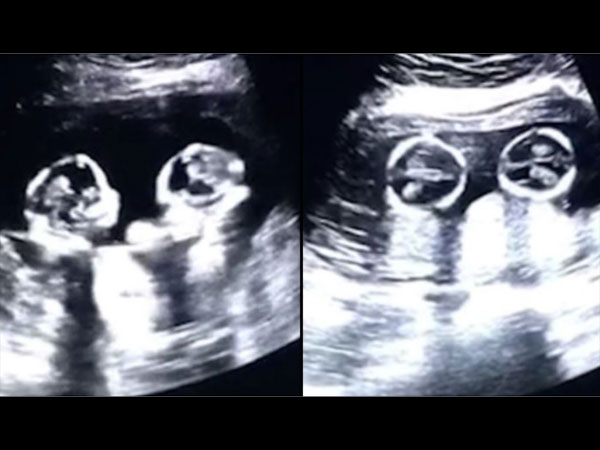

Theo nguồn tin, đoạn video được lan truyền trên mạng xã hội Trung Quốc gần đây được ghi lại bởi người bố đang đưa vợ đi siêu âm. Người vợ đang mang thai 2 bé gái sinh đôi và đang ở tháng thứ 4 trong thai kỳ.

Hình ảnh siêu âm cho thấy 2 thai nhi dường như đang đá và va vào nhau liên tục. Kể từ thời điểm đăng trên Youtube, video được lan truyền rất mạnh mẽ.

Mr.Tao (28 tuổi), người bố của 2 bé gái này đã nói với trang Chinese News rằng anh cảm thấy rất thích thú với hành động của những đứa con chưa chào đời của mình. Anh còn hài hước nói rằng mình như đang xem một trận đấu quyền anh của 2 đứa con gái.